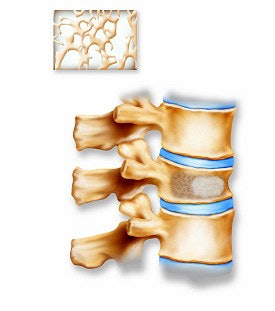

Above, the acrylic bone cement flows into the vertebra, filling the trabecular spaces within the bone. Inset shows a magnified view of the interior of the vertebra with the cement filling in the spaces. Below, the restored vertebra with the hardened cement, stabilizing the vertebral structure and relieving pain. Inset shows magnified view of the interior of the restored vertebra.